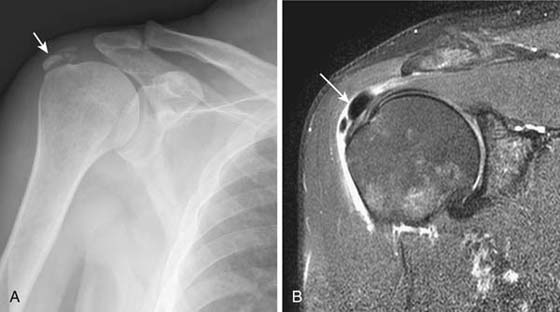

Although shoulder impingement is a clinical diagnosis, it has imaging manifestations that are helpful in guiding treatment. Radiography plays a role in the initial examination of impingement. Subacromial spurs, glenohumeral joint osteoarthritis, and evidence of chronic rotator cuff tear with a high riding humeral head may be identified with radiographs,5 which may further influence management decisions (Fig. 14-6). Noncontrast shoulder MRI is frequently employed in the assessment of impingement. Manifestations of impingement, such as subacromial spur, subacromial/subdeltoid (SASD) bursitis, and rotator cuff tears, are all easily demonstrated on MRI.15-17 Features of a rotator cuff tear that can be assessed on MRI include tear type (full vs. partial thickness), tear location, tear dimensions, tear morphology, tear gap/degree of tendon retraction, and the presence of rotator muscle atrophy (Fig. 14-7).

Instability

Radiography is useful in defining osseous alignment at the glenohumeral joint and may demonstrate a Hill–Sachs or bony Bankart’s lesion. CT also has utility in the assessment of osseous structures after subluxation/dislocation, particularly in evaluation of a subtle Bankart’s fracture with an equivocal MRI or intra-articular osseous fragments.21 CT is useful as a preoperative exam to assess fragment size and displacement. MR arthrography is the most sensitive test for evaluation of most of the causes, manifestations, and sequellae of glenohumeral instability.22-24 It allows for precise evaluation of the capsulolabral and ligamentous complex. Labral tears are diagnosed when intra-articular contrast material tracks into or underneath the labrum. Noncontrast MRI is also very sensitive, although use of a high-field scanner (≥0.7 T) is recommended. Labral tears most commonly associated with instability are anteroinferior or posterior (Fig. 14-9). Superior labral tears that track anterior to posterior (SLAP tears) are well seen with MR arthrography but are not usually associated with instability25,26 (Fig. 14-10). Tendon tears that can be associated with instability, including tears of the long head of the biceps tendon or subscapularis, are also well seen by MR arthrography and noncontrast MRI. Multidirectional instability typically shows no abnormality on imaging modalities, although capacious recesses may be observed.

images

Figure 14-9 Bankart’s and Hill–Sachs lesions. Axial T1 fat-saturated MRI after administration of intra-articular gadolinium (direct MR arthrogram) demonstrates sequelae of anterior shoulder dislocation. The anteroinferior labrum and bony glenoid has been disrupted (white arrow) consistent with a bony Bankart lesion. A bony defect is also seen at the posterior humeral head (curved black arrow) consistent with a Hill–Sachs lesion.